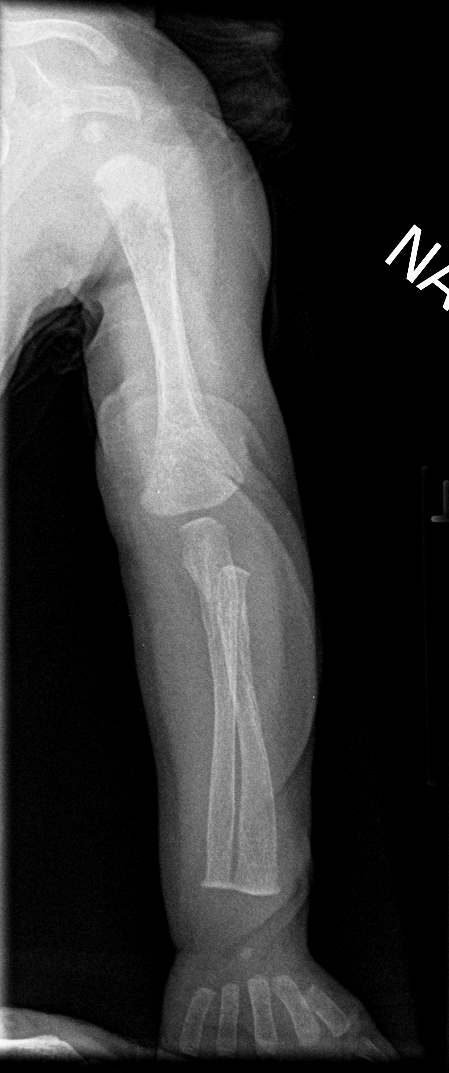

Info Images Findings Impression Reco/Acuity Case Images View Images / Launch Visage Case Notes History 2-month-old presents with decreased right arm movement, increased fussiness, and increased sleepiness for 2 days. Suspected non-accidental trauma. Exam Skeletal survey Prior Study none Dicom View Reference Material

Section 1 Submit Findings CB1550 Findings Skeletal Survey - Technique Check Skull AP/Lat Yes No Cervical and Thoracolumbar spine Yes No Chest X-Ray Yes No Ribs – Left/Right Oblique Yes No Abdominal X-Ray Yes No Pelvis with both hips Yes No Bilateral Humerus, Forearm, Hand Yes No Bilateral Femur, Tibia/fibula, feet Yes No Any additional lateral views of the extremities Yes No The exam is over or under penetrated. Yes No The exam may or may not be limited by overlying structures or soft tissues, body habitus, patient positioning, support devices, or motion. Yes No The area of concern is indicated by the patient, technologist, or care provider. Yes No The area of concern is included on the exam. Yes No Soft Tissues There is soft tissue swelling, indistinctness of fat/muscle planes, gas, or laceration in the area of clinical concern. Yes No There is an effusion, fat pad displacement, or fat fluid level. Yes No There is a radiodense or lucent foreign body. Yes No There are other densities, calcifications, post-surgical changes, or support devices in the soft tissues. Yes No Any support lines/tubes. Yes No Bone There is a break or interruption of the continuity of the cortical or cancellous bone. Yes No There is overriding of the trabeculae with apparent sclerosis. Yes No There is displacement of a fracture fragment. Yes No There is bowing of the bone in addition to the fracture at the apex of the bowed bone concerning for the greenstick. Yes No There is a spiral fracture of the leg concerning for toddler’s fracture. Yes No There is abnormal angulation or bulging of the cortical surface relative to the normal cortex which could be from a buckle or torus fracture. Yes No There is a displaced fragment which may be from avulsion by a tendon, ligament, or joint capsule or from a comminuted or other fracture. Yes No The stress trabeculae or other trabeculae of the cancellous bone are interrupted or otherwise abnormal. Yes No There is subperiosteal or endosteal reaction which could indicate a healing or subacute fracture or other abnormality. Yes No There is hard/soft callus formation. Yes No There is remodeling of the bone. Yes No There is a corner fracture or metaphyseal lesion that could be from nonaccidental trauma. Yes No There are multiple fractures of different ages. Yes No There are vertebral body/spinous process fractures. Yes No There are rib fractures. Location - posterior or lateral. Yes No There is scapular/sternal fracture. Yes No There are fractures of the digits. Yes No There are wormian bones. Yes No There are intrasutural bones. Yes No There is metaphyseal abnormality (lucencies, increased density, erosion) which may be from something other than injury such as stress, metabolic disease (e.g. rickets with loss or distortion of the zone of the provisional calcification), neoplasm (e.g. leukemia), heavy metals, inflammation, or infection. Yes No There are metaphyseal spurs. Yes No There are bony deformities involving multiple bones. Yes No The bones are gracile. Yes No There are non-healing fractures. Yes No There is/are focal or multifocal lytic/lucent, blastic/sclerotic or mixed density lesion(s) or other abnormality. Yes No Overall bone density is increased or decreased with or without thinning or thickening of the cortical or cancellous bone. Yes No Growth plates, ossification centers, apophyses The growth plate(s) is/are abnormal. Yes No There is widening of the physis from a fracture with or without displacement of the epiphysis (Salter-Harris I). Yes No There is a fracture through the physis which then extends into the metaphysis with or without angulation or displacement (S-H II). Yes No There is a fracture through the physis which then extends into the epiphysis and is intra-articular, with or without angulation or displacement (S-H III). Yes No There is a fracture through the metaphysis, physis, and epiphysis which extends into the joint space with or without angulation or displacement (S-H IV). Yes No There is narrowing of the physis from a compression fracture (S-H V). Yes No The apophysis, epicondyle, secondary ossification center, or accessory ossicle is displaced or otherwise abnormal. Yes No The ossification centers are underdeveloped. Yes No Joints and alignment There is an effusion, fat pad displacement, or fat fluid level. Yes No The epiphysis or subchondral bone is fractured, interrupted, flattened, compressed, impacted, displaced, or otherwise abnormal. Yes No There is an intra-articular loose body or chondrocalcinosis. Yes No The joint is widened, narrowed, dislocated, malaligned, or incongruent. Yes No There is pseudoarthrosis. Yes No Other findings There are developmental changes or other anatomic variants or other existing conditions that may or may not be contributing to symptoms which can or should be further evaluated non-emergently or are otherwise incidental. Yes No The remainder of the exam is abnormal for age. Yes No The lungs show focal airspace opacity. Yes No There is pneumothorax. Yes No There is organomegaly. Yes No There is intra-abdominal calcification. Yes No There is displacement of the bowel loops. Yes No There is free intraperitoneal air. Yes No The bowel loops are dilated/obstructed. Yes No There is paraspinal soft tissue abnormality. Yes No